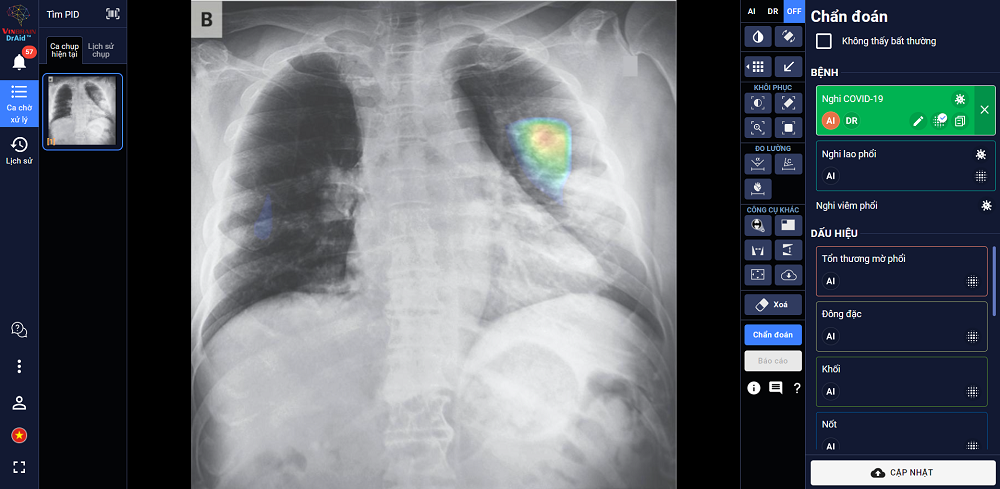

“DrAid for Radiology”– AI Trợ lý Bác sĩ cho Chẩn đoán hình ảnh y tế là sản phẩm đầu tay của VinBrain và cũng là sản phẩm AI hoàn chỉnh đầu tiên của y tế Việt Nam ra mắt phiên bản đầu tiên vào ngày 14/06/2020. Sản phẩm có khả năng phát hiện, sàng lọc trên 21 dấu hiệu bất thường và bệnh lý về Phổi – Tim – Xương trong vòng 5 giây với độ chính xác trên 89%; đồng thời có thể chia sẻ kết quả chẩn đoán thông qua QR code hoặc đường link. Đặc biệt, sản phẩm có khả năng tự cảnh báo COVID-19, kể cả các trường hợp không có triệu chứng hoặc tổn thương phổi nhẹ dựa trên X-quang ngực thẳng, kết hợp cùng xét nghiệm PCR giúp nâng cao độ chính xác, giảm thiểu tình trạng âm tính giả... DrAid cũng nổi bật với tính năng “Hỏi ý kiến Bác sĩ thứ 2 (từ xa)”. Thông qua việc chia sẻ hình ảnh trực tiếp từ DrAid, bác sỹ có thể hội chẩn từ xa với đồng nghiệp hoặc tham khảo ý kiến của các chuyên gia đầu ngành mà không bị ảnh hưởng bởi rào cản địa lý.

DrAid được Ban giám khảo ACM SIGAI đánh giá cao vì sản phẩm đã kết hợp và ứng dụng những kỹ thuật tiên tiến nhất trong lĩnh vực trí tuệ nhân tạo như phân loại nhiều lớp, suy luận theo cấu trúc cục bộ đến tổng quan, học chủ động, đào tạo đối nghịch, mạng nơ ron tích chập phức hợp, nhận dạng giọng nói cho chỉnh sửa báo cáo Y tế tự động, khoanh vùng tổn thương trên ảnh Y tế với kiến thức máy học sử dụng công nghệ cao AI dựa trên mô hình với hàng trăm triệu tham số điểm ảnh (pixel) và dữ liệu lớn hàng triệu ảnh với mỗi ảnh có hàng triệu điểm ảnh (pixel), cùng nhiều kỹ thuật khác tạo nên một dịch vụ trí tuệ nhân tạo phục vụ Y tế toàn diện.